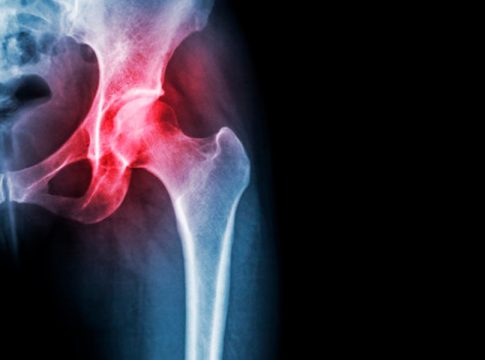

Si la movilidad de la cadera se restringe cada vez más dolorosamente, la causa suele ser una artrosis de cadera: la artrosis es el desgaste creciente del cartílago articular, que afecta gradualmente a los huesos, así como a la función de tendones, ligamentos y músculos.

El movimiento en la articulación de la cadera se vuelve cada vez más doloroso para los pacientes afectados. La articulación de la cadera también puede perder su forma. La articulación se puso rígida.

En la etapa II de la osteoartritis de cadera, el paciente ya tiene dolor de cadera como un dolor inicial o como un bloqueo doloroso del movimiento con ciertos movimientos. Los llamados espolones óseos (osteofitos) se forman dondequiera que los huesos de la osteoartritis de la cadera, ya sea por pinzamiento de la cadera o después de que el cartílago se desgaste, toque y colisione.

Con cada movimiento, estos osteofitos en la articulación de la cadera se colocan sobre la capa opuesta de cartílago en la articulación de la cadera. En algún momento, los huesos de las articulaciones involucradas se frotan entre sí.

Hacen que las superficies de las articulaciones sean ásperas y aceleran significativamente el desgaste del cartílago en la cadera.

La capa de cartílago sirve como capa deslizante y amortiguador. El cartílago mantiene todas las articulaciones flexibles. En el caso de la osteoartritis, esta capa deslizante en la articulación inicialmente se vuelve áspera y agrietada, luego más delgada y más delgada y erosionada.

Si el cartílago se desgasta y los huesos se rozan entre sí (los llamados huesos calvos), también se atacan los huesos, ligamentos y cápsulas articulares de la articulación de la cadera.